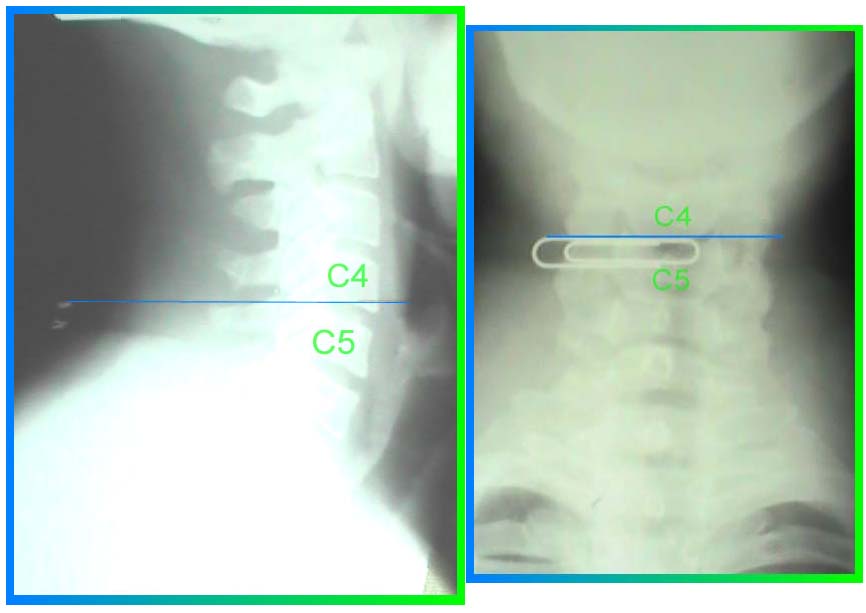

In order to start properly, I palpated the most prominent vertebra in my neck, or upper back. I placed a lead weight on the spot, taped it, and took one AP and one lateral cervicothoracic (CT) x-ray to identify my most prominent vertebra. See below:

When I initially saw the result, I thought that my most prominent vertebra was C6. However, you can plainly see that the spinous process of C7 is the most prominent. However, the point palpated lies on a horizontal line with C6, not C7. This helps to illustrate the complications that arise due to the overlying soft tissue, primarily muscle. The interesting point is thus: due to the declination, back to front, of the C7 vertebra, it's spinous process actually lies in the same vertical plane as the C6 vertebra. This occurs so long as the individual has the normal cervical curve, called a lordosis. For anatomical purposes, landmarks relative to the spine are reference by what vertebral body they are in line with and not the spinous process.

As you can see, the bottom edge of my collar rests at the C4 vertebral level, using the vertebral body as the indicator. The line in the lateral film does cross part of the upper portion of the C5 spinous process, but is considered the C4 vertebral level. This is in a standing, neutral position and is the natural position for my shirt collar to lay upon. You can see that this is the same point where the curvature of my neck begins in a backward, or posterior direction. It is also the same point where the diameter of my neck beings to significantly increase due to the soft tissue mass of the trapezius muscle. The best indicator to where the collar sits is the circumference of the shirt neck as it relates to the human neck. That does not mean that it sits at C6 or C7.